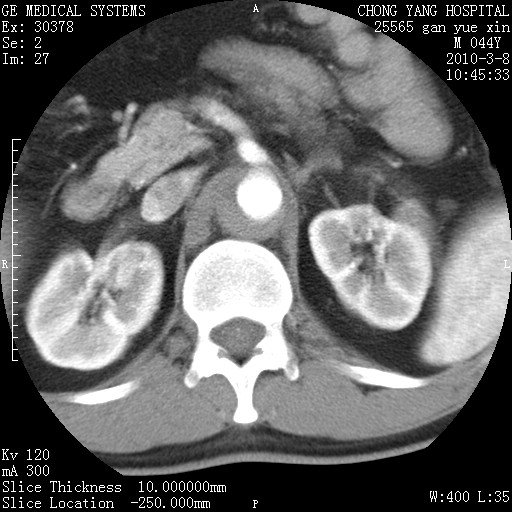

标题: CT24940:主动脉增强,典型病例。 [打印本页]

标题: CT24940:主动脉增强,典型病例。

夹层动脉瘤。

动脉夹层

夹层动脉瘤,典型

主动脉夹层。

动脉夹层的分型:

⒈debakey分型:根据主动脉夹层累及部位,分为三型:ⅰ型:原发破口位于升主动脉或主动脉弓部,夹层累及升主动脉、主动脉弓部、胸主动脉、腹主动脉大部或全部,少数可累及髂动脉。ⅱ型:原发破口位于升主动脉,夹层累及升主动脉,少数可累及部分主动脉弓。ⅲ型:原发破口位于左锁骨下动脉开口远端,根据夹层累及范围又分为ⅲa,ⅲb。ⅲa型:夹层累及胸主动脉。ⅲb型:夹层累及升主动脉、腹主动脉大部或全部。少数可累及髂动脉。

⒉stanford分型:a型:夹层累及升主动脉,无论远端范围如何。b型:夹层累及左锁骨下动脉开口以远的降主动脉。

夹层动脉瘤,少量胸水

夹层动脉瘤;左侧少量胸腔积液。

典型主动脉夹层。